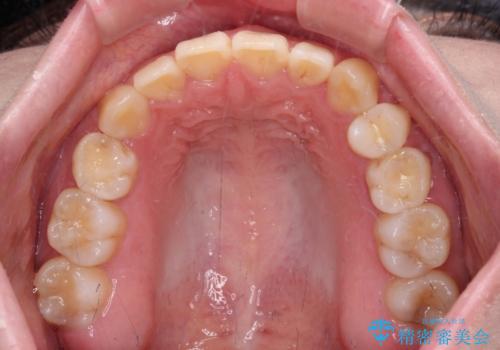

ディープバイトをインビザライン矯正で改善

- 前歯のデコボコと強い咬みしめを気にして来院された患者様です。

インビザラインを用いて、前歯の叢生を解消するとともに、ディープバイトを改善していくこととしました。

上顎に乳歯が左右1本ずつ残っていたため、若干咬み合わせに不具合が残りましたが、強い咬合力の原因であったディープバイトをしっかりと改善することができました。